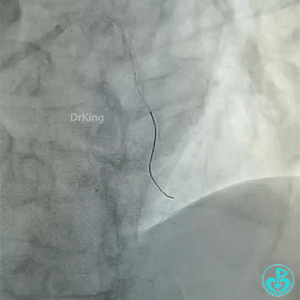

导丝怎么扩真怪!急性心梗前降支导丝通过顺利,球囊扩张后导丝移位很多!不在原来的血管腔!_https://www.jmylbn.com_新闻资讯_第1张

导丝怎么扩真怪!急性心梗前降支导丝通过顺利,球囊扩张后导丝移位很多!不在原来的血管腔!

急性前壁心梗,两小时。

BMW导丝,预扩前导丝是弯曲的,预扩时球囊也是弯曲的,预扩后导丝拉直,血管的弯曲还在。